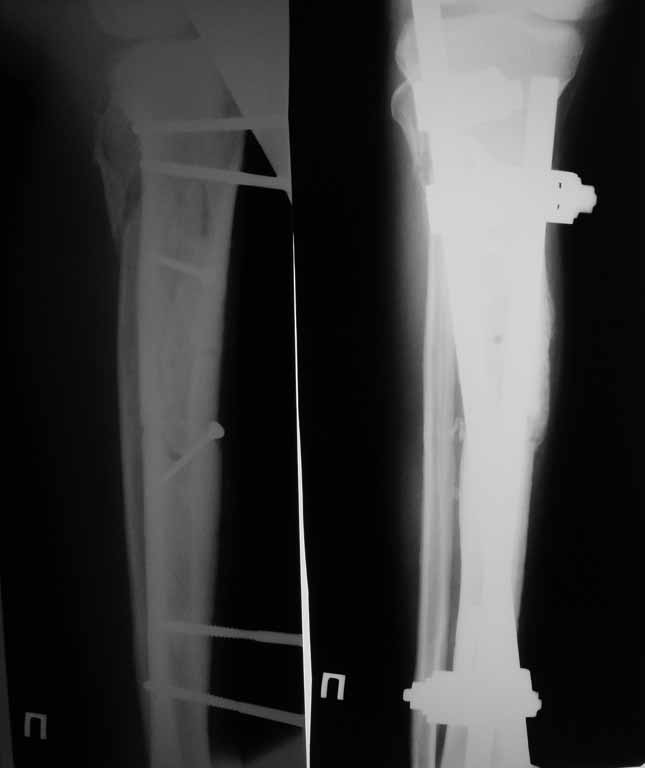

Привожу пример: Пациент с открытой тяжелой ЧМТ.

Диагноз при поступлении: Открытый оскольчатый перелом свода и основания черепа,субдуральная гематома, ушиб головного мозга тяжелой степени. Открытый оскольчатый перелом костей правой голени. Шок 3 Кома 3

По тяжести ЧМТ ( по данным РКТ) выжить был не должен в принципе.

При поступлении оперирован : трепанация, ПХО, остеосинтез голени.

Консолидация в аппарате внешней фиксации к 2 месяцам. Аппарат снят через 2,5 месяца.

Фото в приложении.